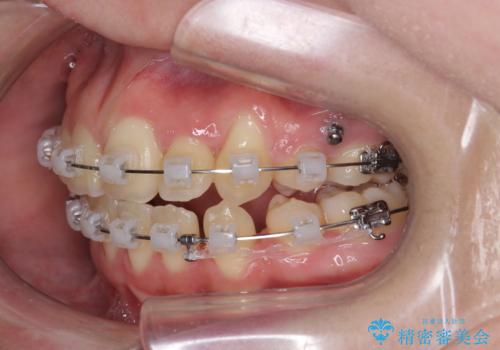

歯並びのせいで歯ブラシがしづらい マルチブラケットを用いた抜歯矯正

- 歯並びのがたつきにより歯ブラシがしづらく、今後虫歯になってしまう不安から、矯正治療を希望されて来院されました。

歯を並べるにはスペースが不足しているため、小臼歯の抜歯を4本行うマルチブラケット矯正による治療を計画します。

治療後は非常に歯ブラシがしやすくなったと、治療結果に満足いただくことができました。